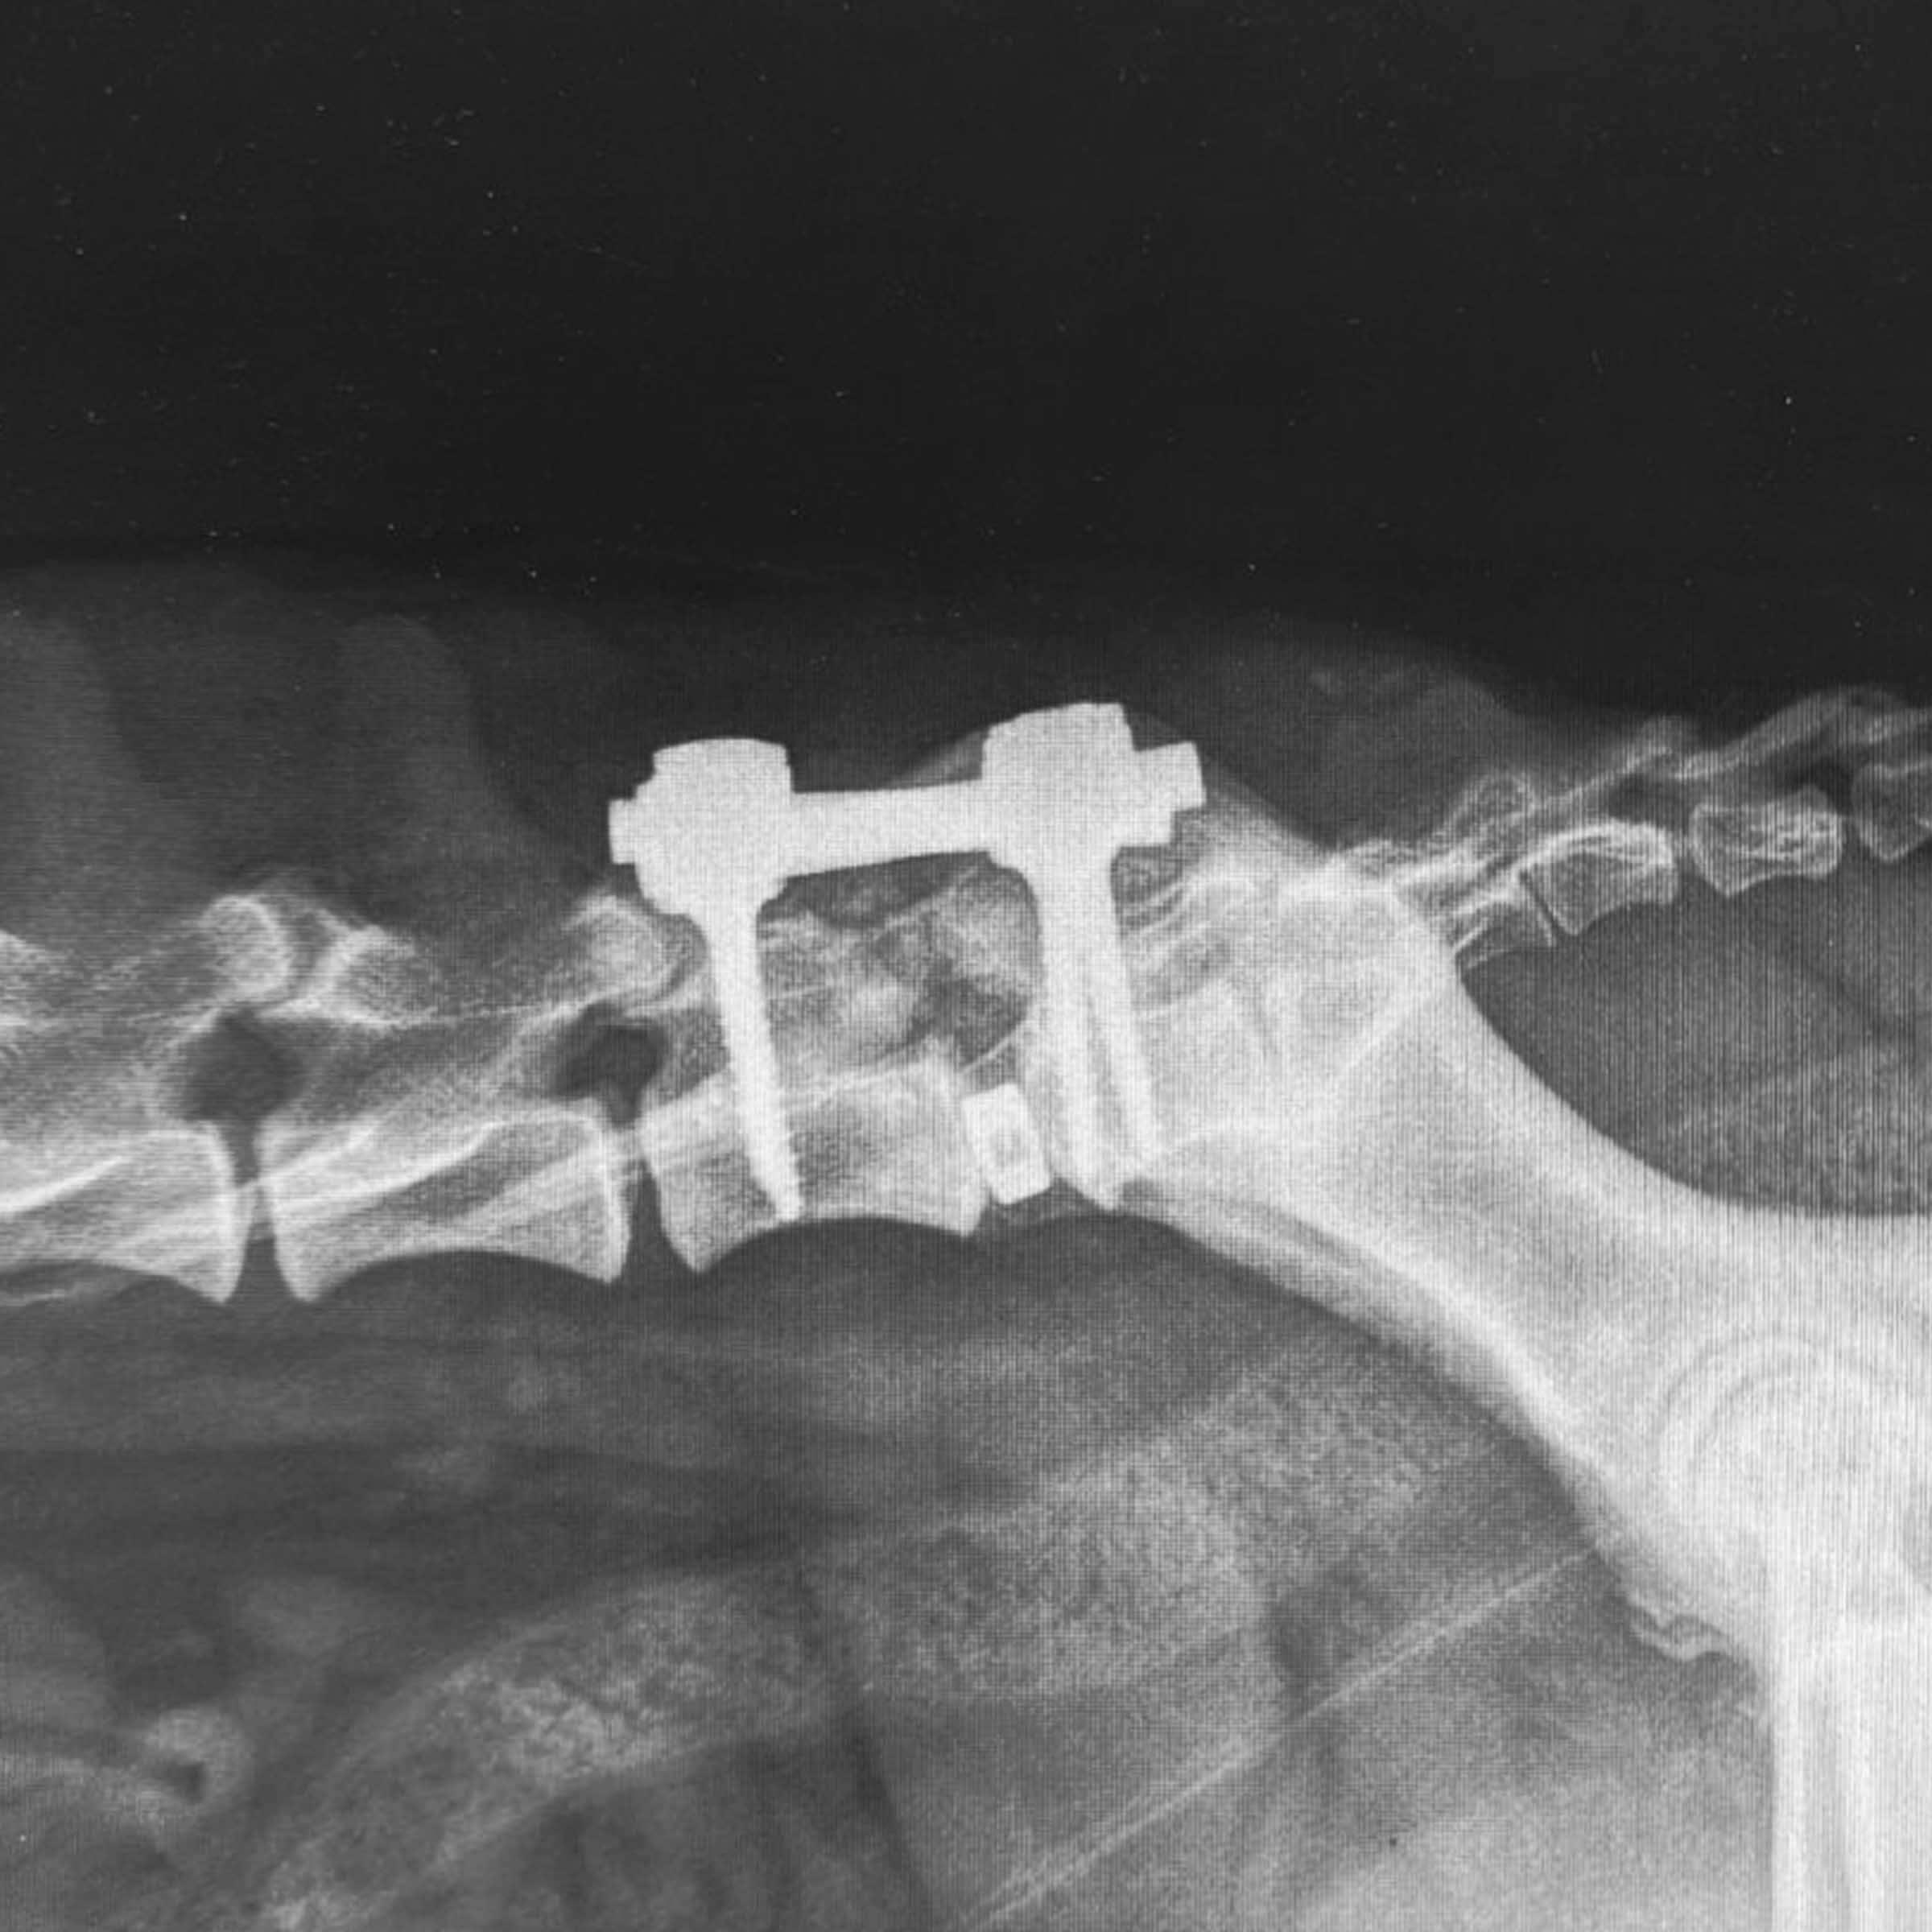

Case Overview In November 2025, Skeeter, a 14-week-old Doodle puppy weighing ...